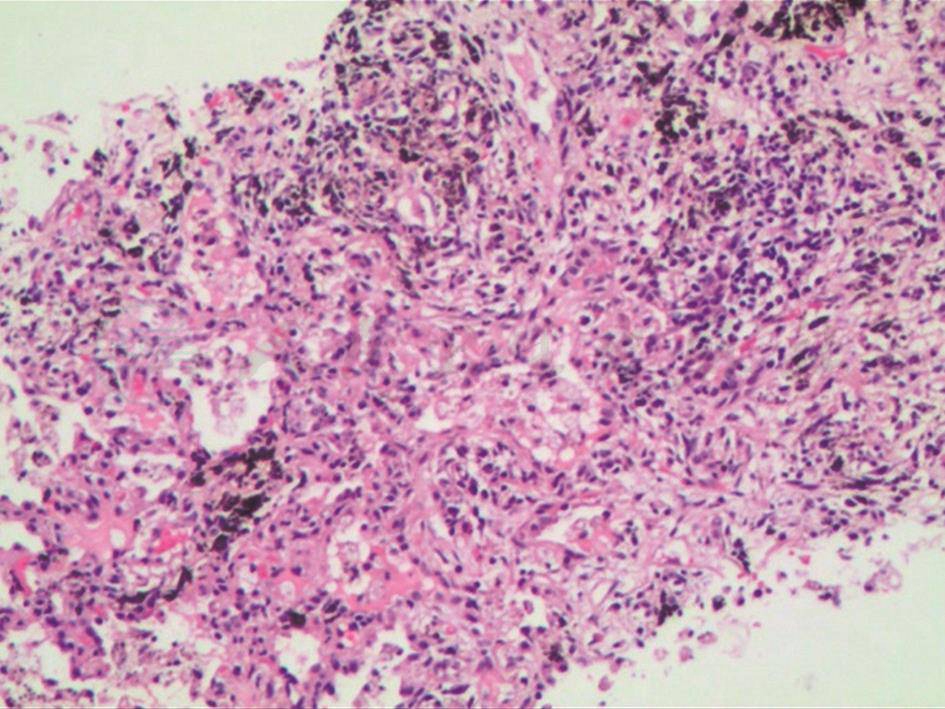

CT引导下经皮穿刺肺活检病理检查(入院后第4天):送检右下肺穿刺活检组织,显微镜下见肺泡间隔增宽、纤维化,有慢性炎症细胞浸润及炭末沉着,肺泡腔内见较多吞噬细胞,未见其他异常表现(图4)。

图4 右下肺穿刺活检组织病理表现(HE染色,200×)